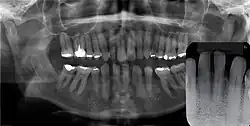

Gingival cyst of adult is a rare condition. The incidence is less than 0.5%. It is formed from the rests of dental lamina.[11] It is found in the soft tissues on the buccal and labial portions of the jaw. It usually occurs on the facial gingiva as a single small flesh colored swelling, sometimes with a bluish hue due to the cystic fluid. Sometimes, it may occur in cluster, either unilaterally or bilaterally or on the lingual surface of the alveolar process. It is most commonly seen in the canine and premolar regions of the mandible, and are sometimes confused with lateral periodontal cysts.[12] It is not normally problematic, but when it grows larger, it can cause some discomfort. It can be removed by simple surgical excision. They are developed late in life, generally up to the sixth decade of age.[1]